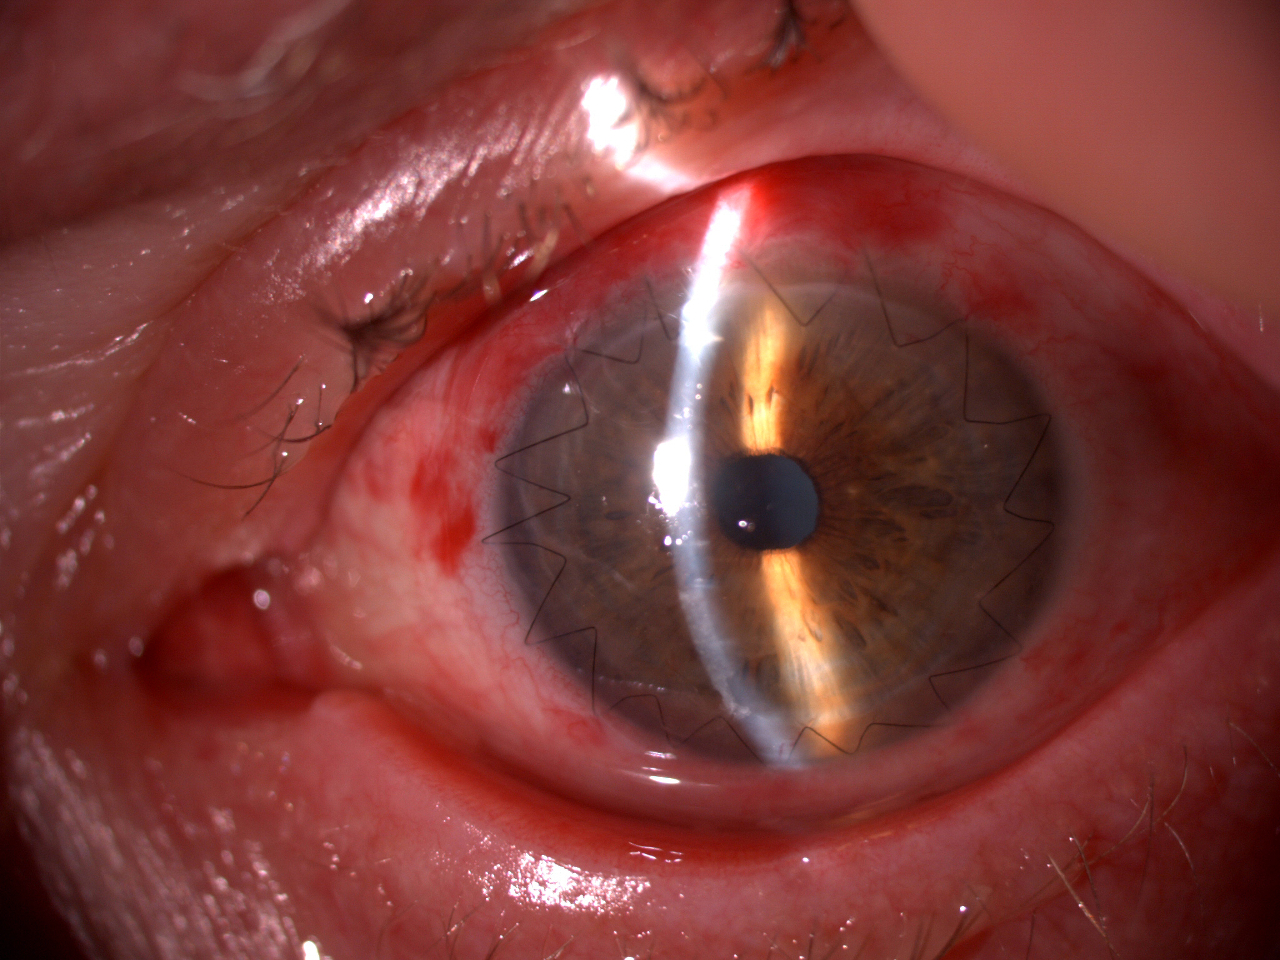

Paziente con cheratopatia bollosa pseudofachia e aniridia operato di trapianto endoteliale (DSAEK).

Il lembo è ben posizionato e la cheratopatia bollosa è regredita.